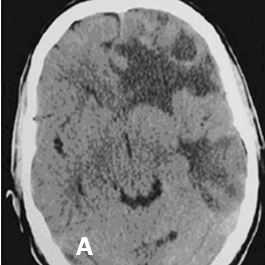

Hình 1. Hình ảnh di căn não đa ổ trước tiêm thuốc (A) và sau tiêm thuốc (B) của bệnh nhân ung thư phổi không phải tế bào nhỏ.

Trước tiêm thuốc: Tổn thương thường là khối đồng hay giảm tỉ trọng. Đôi khi có tỉ trọng cao hơn vùng nhu não liền kề như trong trường hợp chảy máu trong u di căn hoặc lắng đọng canxi.

Sau tiêm thuốc: Tổn thương ngấm thuốc dạng lốm đốm, dạng nốt hay hình vòng.